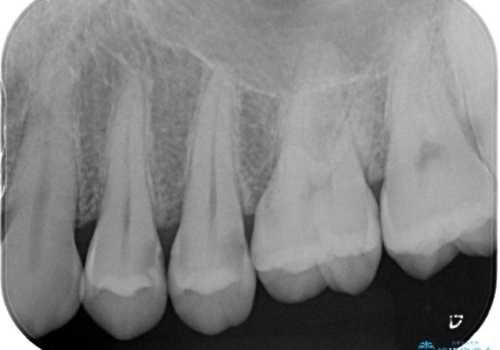

- ホワイトニング希望で来院された患者様ですが、口腔内をチェックしたところ2歯虫歯が見つかりました。無症状ではありましたが、レントゲン画像でも歯髄(歯の神経が内蔵されている場所)近くまでの広がりが確認できました。ランクの高い材料で治療したいとのご要望もあり、変形の少ないシリコン材料を使用した、生体親和性の良いセラミックインレーにて治療を完了しました。術後も症状等なく経過良好です。